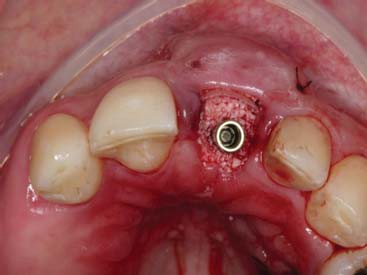

Simultaneamente, foi realizada a exodontia do elemento 21, seguida da instalação do implante com toque final de 30N. O espaço alveolar remanescente foi preenchido primeiro com o enxerto de conjuntivo associado a uma membrana de colágeno reabsorvível (GenDerm – Baumer), juntamente com material de substituição óssea (Geistlich Bio-Oss, Geistlich Pharma) (figura 7 e figura 8).

Finalizado toda a parte cirúrgica foi feito o posicionamento de um cilindro provisório e da tampa de cobertura que havia sido confeccionado no gesso e feita a união com resina tipo flow, seguindo do acabamento e polimento fora da boca. Uma vez pronto o cicatrizador personalizado, este foi instalado com o torque de 15N e uma prótese parcial removível provisória foi instalada (figura 9, figura 10, figura 11, figura 12, figura 13 e figura 14).